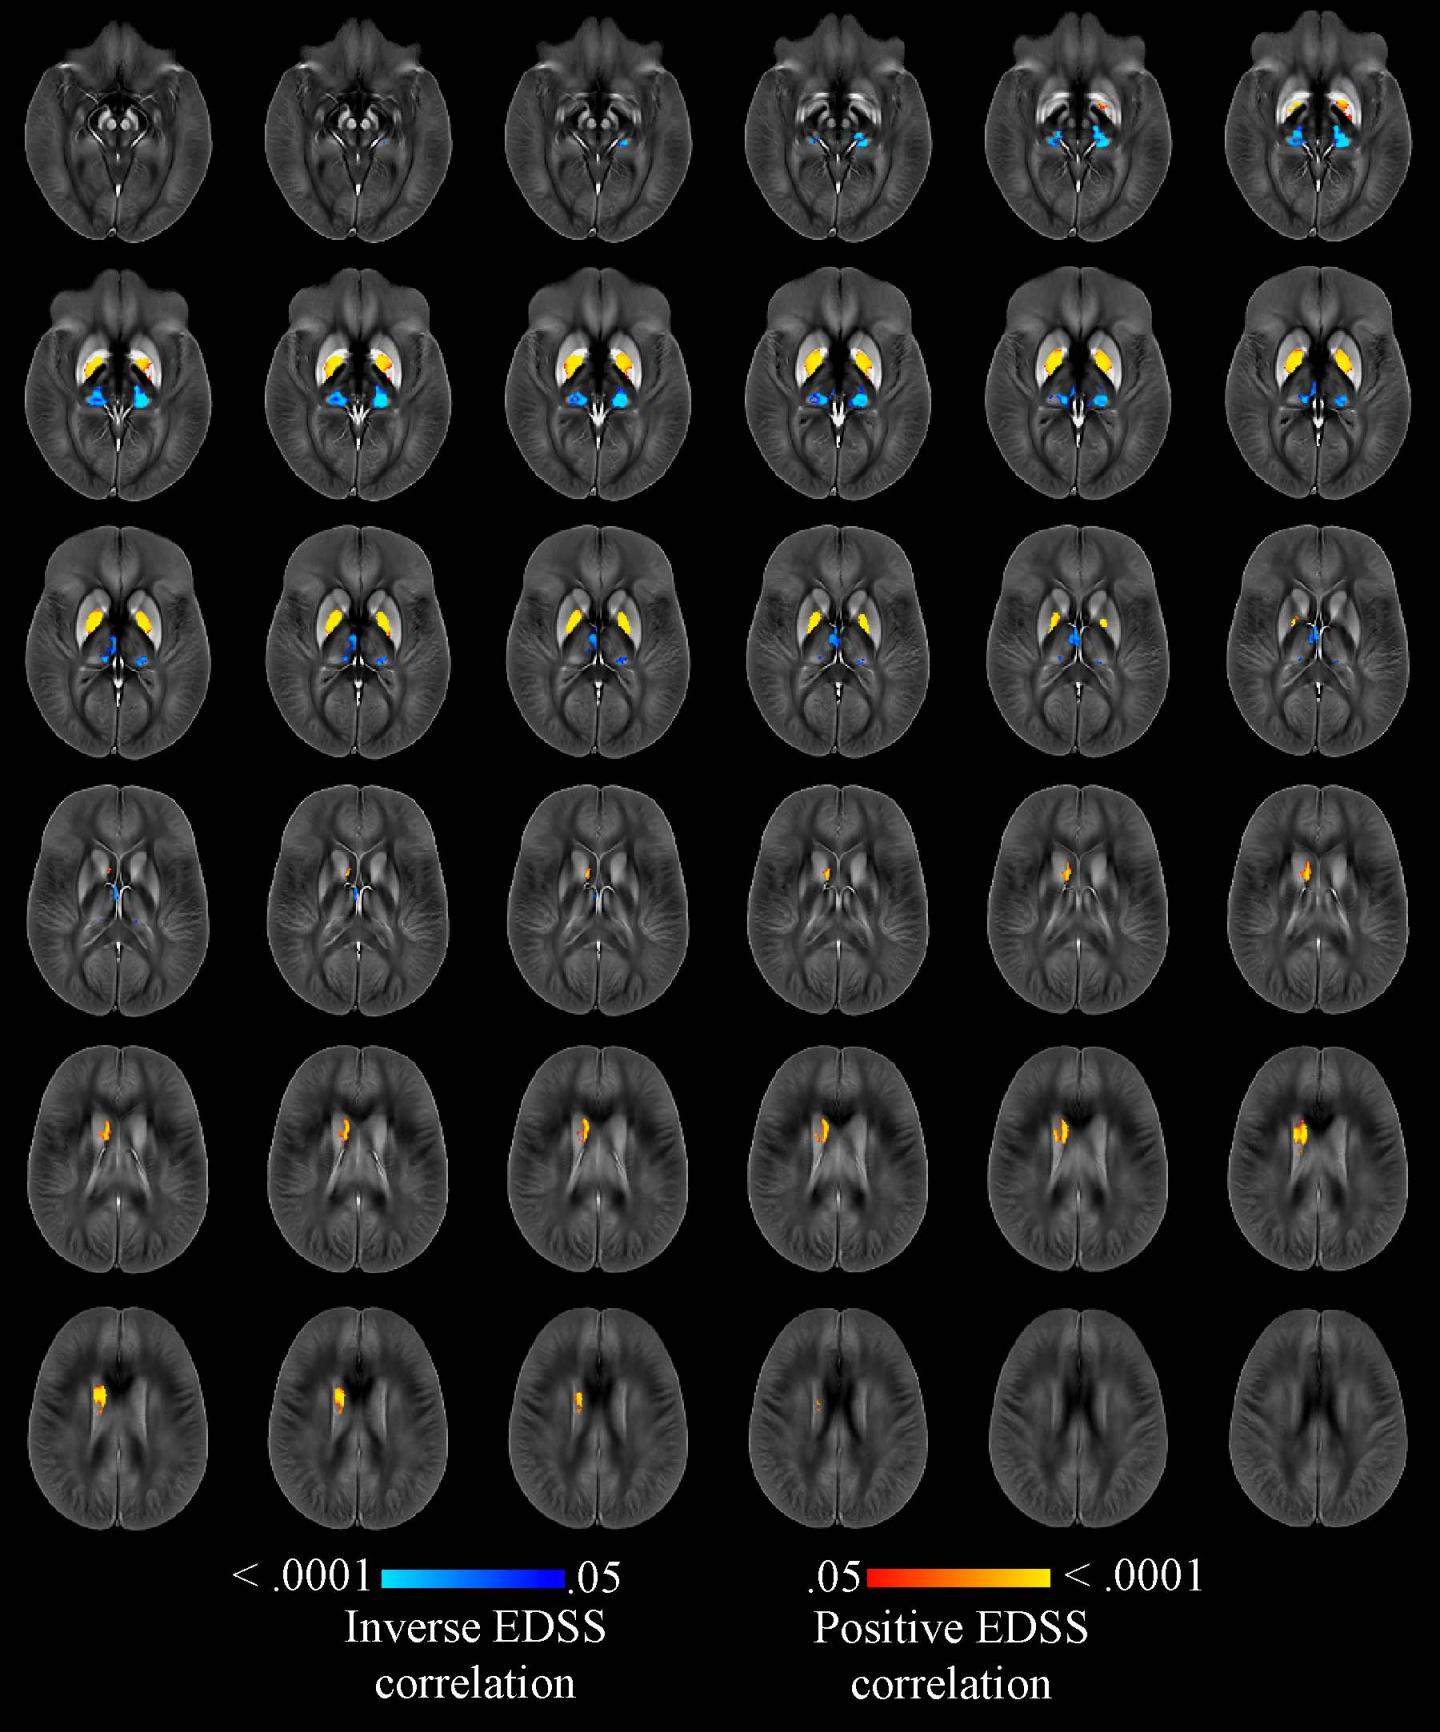

Dr. Zivadinov and colleagues recently compared brain iron levels in people with MS to those of a healthy control group using an advanced MRI technique called quantitative susceptibility mapping. A brain region with more iron would have higher magnetic susceptibility, and one with less iron would have lower susceptibility.

The researchers performed the mapping technique on 600 MS patients, including 452 with early-stage disease and 148 whose disease had progressed.

Compared to 250 healthy control participants, MS patients had higher levels of iron in the basal ganglia, a group of structures deep in the brain that are central to movement. However, the MS patients had lower levels of iron in their thalamus, an important brain region that helps process sensory input by acting as a relay between certain brain structures and the spinal cord. The lower iron content in the thalamus and higher iron content in other deep gray matter structures of people with MS were associated with longer disease duration, higher disability degree and disease progression.

This association with clinical disability persisted even after adjusting for changes in the brain volumes of each individual structure.

"In this large cohort of MS patients and healthy controls, we have reported, for the first time, iron increasing in the basal ganglia but decreasing in thalamic structures," Dr. Zivadinov said. "Iron depletion or increase in several structures of the brain is an independent predictor of disability related to MS."

"Susceptibility is an interesting imaging marker of disease severity that can predict which patients are at severe risk of progressing," Dr. Zivadinov said. "To be able to act against changes in susceptibility would be extremely beneficial."